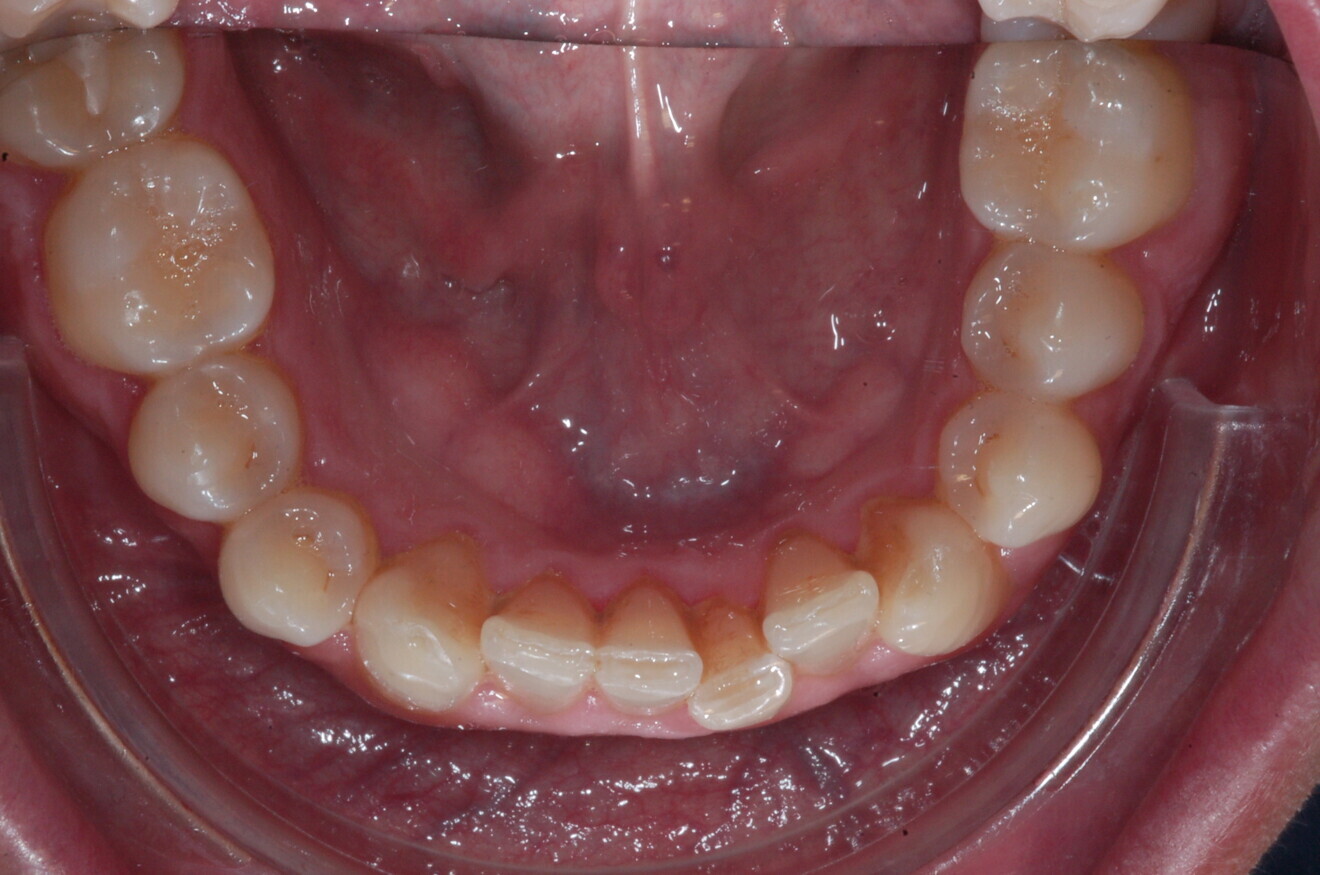

The digital treatment plan (ClinCheck) provided 12 aligners for the maxillary arch and 17 for the mandibular arch. The treatment objectives were focused on coupled vertical movements of posterior extrusion and anterior intrusion by means of bite ramps, providing for posterior disocclusion and anterior intrusion of mandibular teeth by means of extrusion attachments needed for mandibular arch levelling. The maxillary and mandibular incisors were proclined to level the upper and lower curve of Spee and to support the flat profile and the lips. Class II elastics were planned to support mandibular proclination and heavy posterior occlusal contacts with relative posterior extrusion. Lateral and posterior maxillary torque were planned to be close to 0°, to achieve wider arch design and ideal intercuspation. No digital over-engineering was planned in the set-up. Because of the age of the patient, the aligners were changed every ten days for a treatment time of less than six months. At the end of the first stage of aligners (Figs. 20–24), an additional stage was planned to improve molar intercuspation without elastics with a digital plan of five further aligners. This brought the total treatment time to 7.5 months since the additional aligners were changed every week.

At the end of the treatment, Class I canine and molar relationships were obtained, maxillary incisor inclination was slightly increased (Ui–FH = 112°), mandibular incisor inclination (IMPA = 97.09°) was fully corrected by means of proclination and the divergency was slightly increased (SN–GoGn = 27°) because of the relative posterior extrusion and use of Class II elastics—a small variation (1°), which is interesting considering the age of the patient (Figs. 25–35). A balanced smile arc was obtained with an ideal relationship between the maxillary incisors and lower lip, and torque control of the lateral and posterior segments generated a broader smile.

A 37-year-old male patient presented with the chief need for re establishing anterior alignment in both arches. Facial analysis showed a short face with a flat profile but proper chin projection (Figs. 9–12), and clinical examination revealed a skeletal Class I (ANB = 0.89°) and dental Class I malocclusion with severe deep bite (almost 100%), a deep curve of Spee, normal maxillary central incisor torque (Ui–FH = 110°), mild maxillary crowding and moderate mandibular crowding (Figs. 13–18). The deep bite components were represented in this patient by the severe skeletal condition of hypo divergent pattern (FMA = 14.24°) with normal maxillary and mandibular incisor inclination and decreased gonial angle (110.46°). Analysis of the cephalometric radiograph indicated a reduced lower anterior facial height, combined with a hypo-divergent pattern (Fig. 19). The only treatment option suggested was orthodontic treatment with aligners for deep bite correction with all the features described (bite ramps, pressure area, 3D curve of Spee levelling, Class II elastics and heavy occlusal contacts).